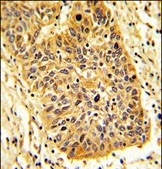

- Formalin-fixed and paraffin-embedded human lung carcinoma reacted with RIOK1 Antibody (N-term), which was peroxidase-conjugated to the secondary antibody, followed by DAB staining. This data demonstrates the use of this antibody for immunohistochemistry; clinical relevance has not been evaluated.